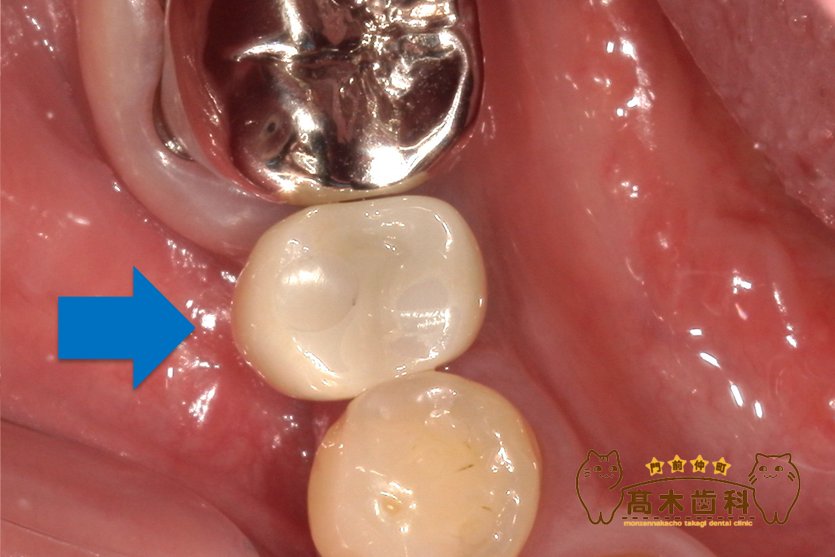

インプラント治療の症例

インプラント埋入手術

症例の詳細はこちら